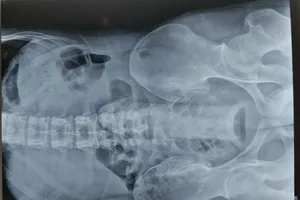

Bé gái 5 tuổi nuốt nam châm trong lúc ăn cơm

Nam thanh niên bị kẹt đồ chơi tình dục trong trực tràng